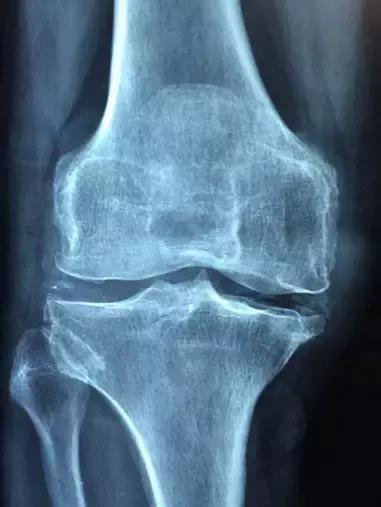

之前有一个老外朋友抱怨自己的中国太太生完孩子后坐月子真麻烦,说西方人从来不坐。但是他也承认,西方的女人老了后有很多人得关节性的疾病。

所以,不是坐月子没有用,也不是西方人不坐月子就没事,而是西医多数对症下药,他们往往在女人出了疼痛之后治疗疼痛,而不会把这些关节性疾病跟数十年前生孩子相联系。

中医认为,一般情况下,中国人的骨节是闭合的,而产后,随着骨盆的打开,产妇全身上下的筋骨腠理都处于一种开放松弛的状态。这时,风寒就容易趁虚而入,通过张开的骨节进入人体内。月子结束时,产妇的骨盆和全身的筋骨腠理都会逐渐恢复到正常的闭合状态。那么,坐月子期间进入体内的寒邪也就会随之而然地被闭锁在体内,从此留下严重的后患。

身体羸弱的产妇,有可能在月子结束后不久就会感到腰酸背痛;而大多数女性在年纪大时,会感觉全身疼,尤其是骨节疼;甚至有的人会疼痛一生。中医上称这种疾病为“产后风”,即月子病。

中医有句话,“月子病,月子治”。意思是上次坐月子时落下的月子病,只能待到下次坐月子时才能进行医治。因为只有到下次坐月子时,人全身的骨节才能再次打开,达到自然松开的状态。趁此机会,施以药石,将寒邪赶出,治好疾患。